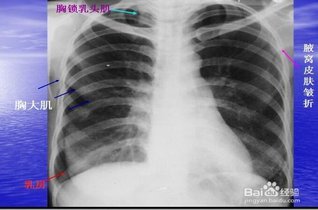

学会看胸片是临床医生必备的技能之一,首先,看胸壁的X线表现,观察胸壁软组织有大的肿块,有皮下积液、积气,同时观察肋骨的连续性是否有中断,这是肋骨骨折的X线征象...73227人收听

在临床上胸部X光片检查是常用的一种检查方法,它是利用X线产生图像,从而观察胸部的病变。胸片的观察需要按一定的顺序,一般可以按照从上往下的顺序,观察双肺上叶...1人收听